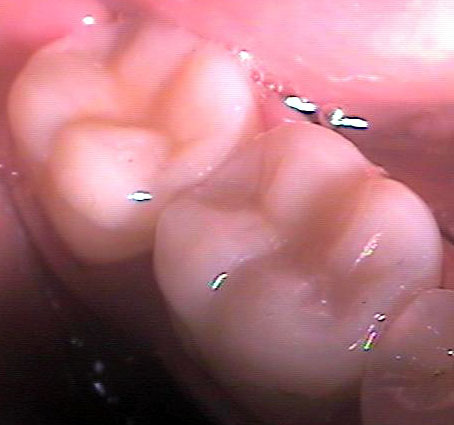

Композитните индиректни възстановявания (т. нар. вставки) са добро решение за възстановяване на кариозни дефекти с по-голям обем. Терминът вставка има руски произход - води началото си от глагола вставлять, който означава поставям. Тъй като през 60-те и 70-те години на ХХ век са се изработвали доста метални вставки, а тогава рускоезичната литература е била най-широко разпространена, е разбираемо защо терминът вставка се използва в българската дентална медицина и до днес. На снимката горе са показани две композитни вставки на зъби 46 и 47. При двата зъба остатъчните странични зъбни стени са били твърде изтънели, което е принудило лекуващия дентален лекар да ги намали на височина. Това се прави с цел вставката да покрие зъба и да го предпази от бъдещо фрактуриране. В този случай цялата дъвкателна повърхност на зъба е изградена от композитен материал.

На снимката горе е показан предишният случай, заснет в по-близък план. Зъботехникът се е постарал да осигури добър оклузален моделаж. Механичната здравина при композитните вставки значително надвишава тази на директните възстановявания. Същевременно керамичните и металните вставки са още по-здрави от композитните. Първенец по отношение на механичната здравина е металната вставка. За съжаление тя е на последно място по естетика - повечето пациенти възприемат крайно негативно металния блясък на този вид конструкции. Тъй като зъботехникът изработва вставката върху гипсов модел, в случая формата на зъба с неговия екватор и контактни точки може да бъде възпроизведена много по-прецизно, отколкото зъболекарят може да извърши при клинични условия. Изработват се изпъкнали и широки екватори, които защитават зъбния венец от механични травми от храната и в същото време изпълват междузъбните амбразури, което предпазва от задържането на хранителни остатъци.